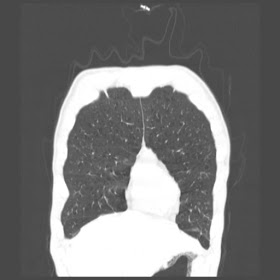

A 52 Years old man suffering with chest pain since 3 years

HRCT Chest